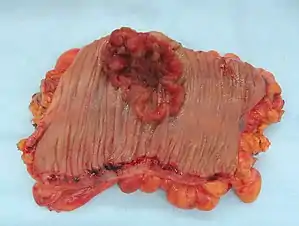

Colorectal cancer

Drinking may be a cause of earlier onset of colorectal cancer.[56] The evidence that alcohol is a cause of bowel cancer is convincing in men and probable in women.[57]

The National Institutes of Health,[58] the National Cancer Institute,[59] Cancer Research,[60] the American Cancer Society,[61] the Mayo Clinic,[62] and the Colorectal Cancer Coalition,[63] American Society of Clinical Oncology[64] and the Memorial Sloan-Kettering Cancer Center[65] list alcohol as a risk factor.

A WCRF panel report finds the evidence "convincing" that alcoholic drinks increase the risk of colorectal cancer in men at consumption levels above 30 grams of absolute alcohol daily.[66] The National Cancer Institute states, "Heavy alcohol use may also increase the risk of colorectal cancer"[67]

A 2011 meta-analysis found that alcohol consumption was associated with an increased risk of colorectal cancer.[68]